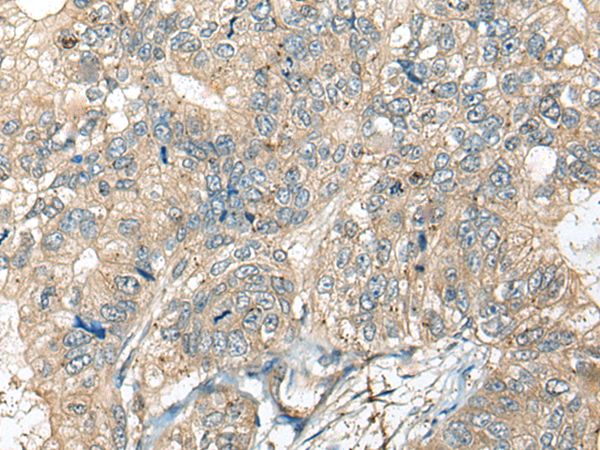

IHC positive control: |

Human gastric cancer and Human liver cancer |

IHC Recommend dilution: |

50-300 |